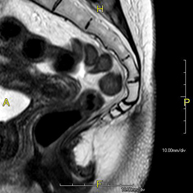

- Sacrum-coccyx MRI

This non-invasive diagnostic procedure uses an electromagnetic field and radio waves (from a transmitter and receiver) to acquire high-definition anatomical images of the sacrum and coccyx. It is a radiation-free procedure. Indicated for: sacrococcygeal pain, trauma.